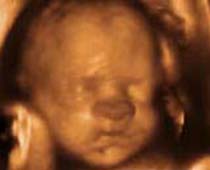

- Fetal Face Ultrasound Photos

- 3D Fetal Profile Ultrasound Scan Photos